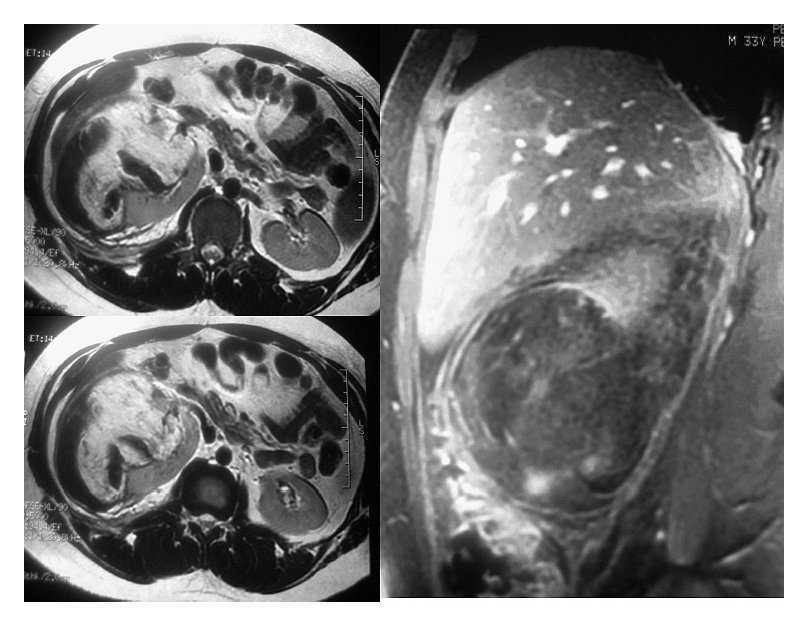

Una vez en mejor estado general se realizó tomografía axial computarizada que mostró una imagen de un tumor renal derecho de 10 UH heterogéneo que desplazaba en sentido posteroinferior y medial al riñón (Imagen 1). Las dimensiones del tumor fueron de 15 cm en sentido longitudinal y 10 cm en sentido transversal, de características heterogéneas con un refuerzo de -30 UH al administrar medio de contraste, lo que aumentó la sospecha de angiomiolipoma renal. Se realizó resonancia magnética con reconstrucción vascular, en la cual se observó hiperintensidad en T1, isointensidad en T2, sin delimitar el tumor y con sangrado con dimensión aproximada de 6-7 cm de diámetro (Imagen 2). En la angiorresonancia se observó pobre vasculatura, incrementando la sensibilidad diagnóstica para angiomiolipoma (Imagen 3).

Imagen 1. TAC abdominal simple.